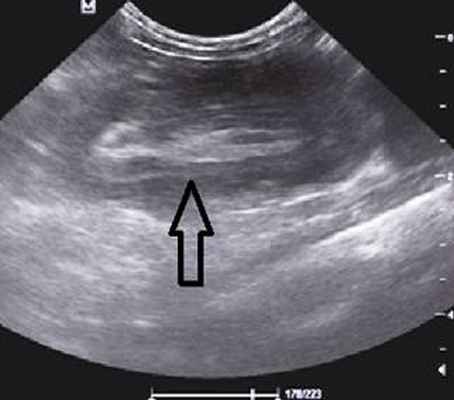

На рисунках 2 и 3 отображена ультразвуковая картина кишечной инвагинации.

Рис. 2. Симптом «мишени»

В момент УЗ-исследования врач может определить один из симптомов:

- симптом мишени (за счёт внедрения одной кишки в другую инвагинат на срезе выглядит как мишень);

- симптом "почки с завоздушенным центром".